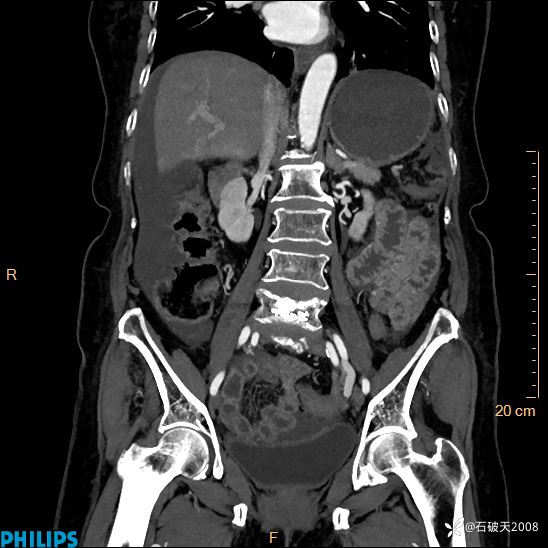

半年前住院没发现问题,近期腹痛来诊

女82岁 主 诉:腹痛半月,加重3天

静脉期